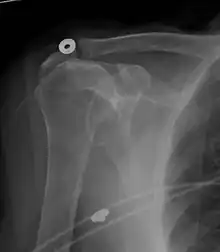

Xray

X-ray projectional radiography cannot directly reveal tears of the rotator cuff, a 'soft tissue', and consequently, normal X-rays cannot exclude a damaged cuff. However, indirect evidence of pathology may be seen in instances where one or more of the tendons has undergone degenerative calcification (calcific tendinitis). The humeral head may migrate upward (high-riding humeral head) secondary to tears of the infraspinatus, or combined tears of the supraspinatus and infraspinatus.[51] The migration can be measured by the distance between:

- A line crossing the center of a line between the superior and inferior rims of the glenoid articular surface (blue in image).

- The center of a "best-fit" circle positioned over the humeral articular surface (green in image)

Normally, the former is positioned inferiorly to the latter, and a reversal therefore indicates a rotator cuff tear.[51] Prolonged contact between a high-riding humeral head and the acromion above it may lead to X-ray findings of wear on the humeral head and acromion; secondary degenerative arthritis of the glenohumeral joint (the ball and socket joint of the shoulder), called cuff arthropathy, may follow.[50] Incidental X-ray findings of bone spurs at the adjacent acromioclavicular joint may show a bone spur growing from the outer edge of the clavicle downward toward the rotator cuff. Spurs may also be seen on the underside of the acromion, once thought to cause direct fraying of the rotator cuff from contact friction, a concept currently regarded as controversial.